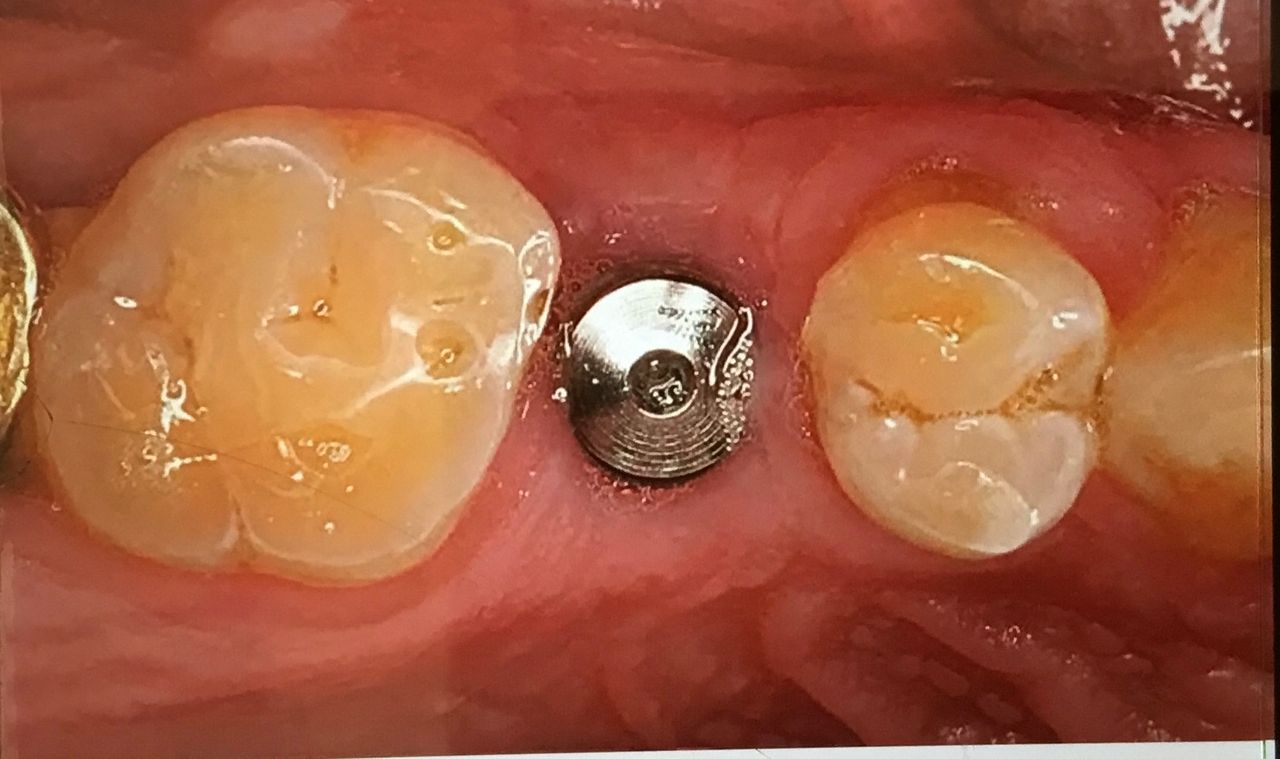

La realización de coronas dentales debe ser exclusivamente por un experto.La corona dental da protección y estética a un diente, no siempre requiere de tratamiento de endodoncia, solo en algunas ocasiones. El procedimiento requiere de mucha precisión para lograr una corona dental perfectamente bien sellada, de acuerdo a los mas recientes artículos científicos 8 de 10 coronas no sellan a la perfección.Anteriormente se realizaban coronas de metal con porcelana las cuales al cabo de un tiempo cambiaban de color y presentaban corrosión en el diente, en la actualidad contamos con diversos tipos de coronas realizadas por medio de CAD CAM zirconia, porcelana y otros materiales de alta calidad.